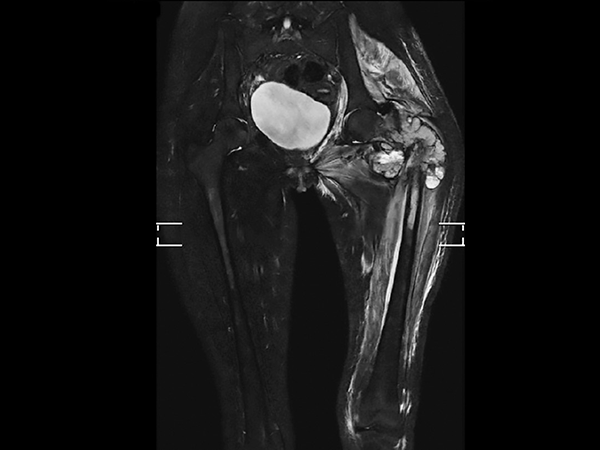

Preoperative MRI in this young girl demonstrates the large tumor with a necrotic component and areas of fluid. The tumor extends down into proximal part of femur. Edema is seen along the femoral shaft down to the knee and in the gluteal muscle. T2W mDIXON TSE in-phase and water images show the superb fat suppression of mDIXON TSE. The two-station MobiView also demonstrates the high quality mDIXON TSE fat suppression over large region and both images with and without fast suppression are obtained in about half the time needed for conventional scans.

Coronal T2w TSE mDIXON (in-phase)